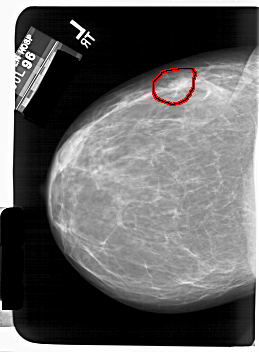

FILE: A_1408_1.LEFT_MLO.OVERLAY

TOTAL_ABNORMALITIES 1

ABNORMALITY 1

LESION_TYPE MASS SHAPE OVAL MARGINS CIRCUMSCRIBED

ASSESSMENT 4

SUBTLETY 4

PATHOLOGY BENIGN

TOTAL_OUTLINES 1

BOUNDARY